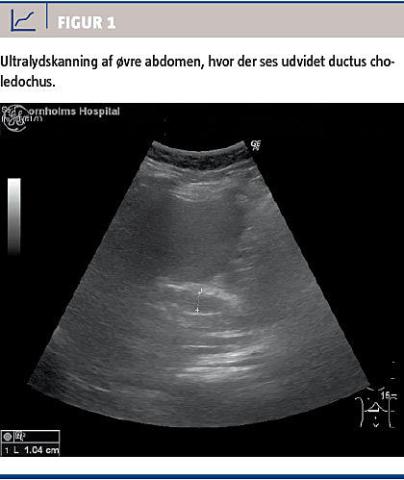

Ved en akut ultralydskanning af abdomen påviste man galdesten uden fortykkelse af galdeblærevæggen og dilateret ductus choledochus til omtrent 10 mm (Figur 1).

Acute pancreatitis is uncommon in children and the spectrum of etiologies is broader than in adults. Here we describe a case of acute, severe gallstone pancreatitis in an obese, 13-year-old girl presenting with upper abdominal pain and markedly elevated levels of amylase and transaminases. Abdominal ultrasound showed cholelithiasis and dilation of the common bile duct; and an endoscopic retrograde cholangiopancreatography with papillotomy was performed. The girl was discharged for elective laparoscopic cholecystectomy.